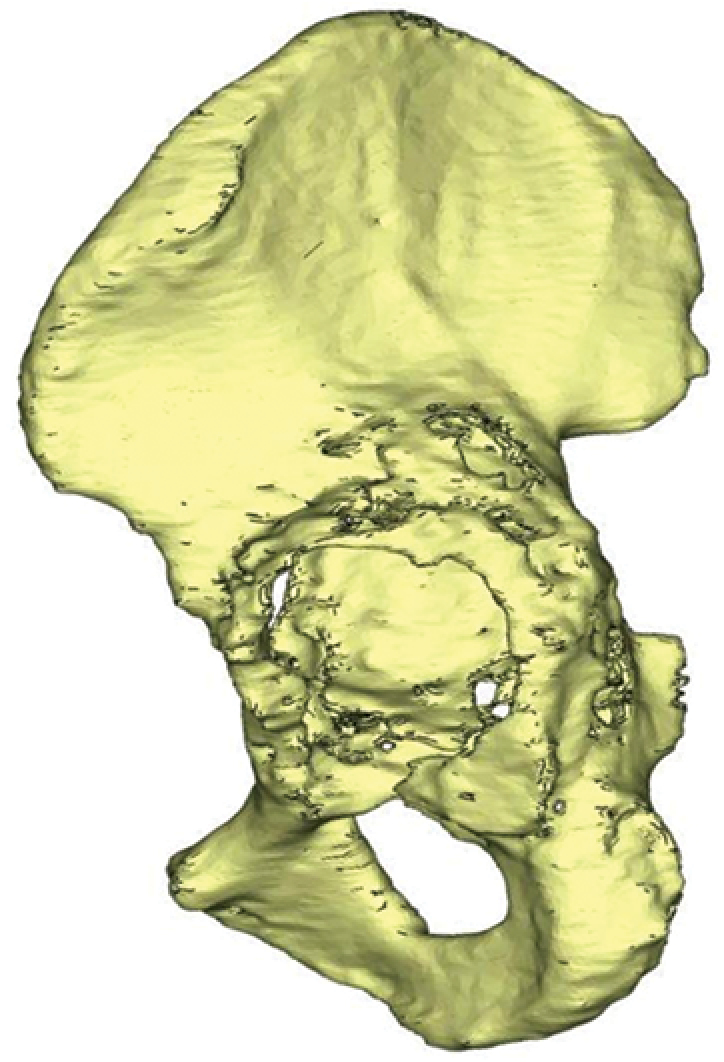

A wide range of surgical implants and their combinations were used, including jumbo cups, modular augments, antiprotrusio cages, cap-cages, and various patient-specific solutions for acetabular reconstruction. The evaluation of treatment outcomes was not within the scope of the present study. Based on the CT data, 3D reconstructions of the pelvis were created. The following acetabular supporting structures were assessed: the iliac wing, anterior column, posterior column, medial wall, and ischium. Each structure was evaluated according to three levels of integrity: anatomically pre-served, partially preserved/lytic destruction, and complete loss of support/full defect.

The analysis of acetabular defects classified as type 3B according to Paprosky in patients indicated for revision of the acetabular component revealed that isolated defects of individual supporting elements of the acetabulum were practically not observed. Such defects were usually combined either with complete destruction of other supporting structures or with lytic bone lesions of varying severity. Therefore, all defects of the supporting elements without complete destruction of at least one of them were grouped separately. Since the analysis included defects with a high migration of the rotation center, all cases demonstrated varying degrees of destruction of the iliac wing.

Thus, five variants of defects were identified (Table 2):

1) lytic defects with partial destruction of the acetabular supporting elements;

2) complete defects of the anterior column with complete or partial preservation of the medial wall and posterior column;

3) complete defects of the medial wall with complete or partial preservation of the anterior and posterior columns;

4) combination of complete defects of the medial wall and anterior column with complete or partial preservation of the posterior column;

5) combination of complete defects of the medial wall and posterior column with complete or partial preservation of the anterior column.

Three-dimensional reconstructions of the pelvis of the same patients from the side of defect | ||||